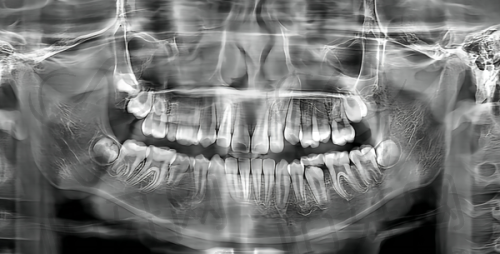

此外,医院还配备了精良的口腔综合治疗台、口腔X光机等设备。口腔综合治疗台具有多种功能,可以满足不同口腔治疗的需求。口腔X光机可以为医生提供清晰的口腔影像,帮助医生更好地诊断口腔疾病。这些设备的使用,不仅提高了医院的诊疗水平,也为患者提供了更加优质、效率高的口腔诊疗服务。